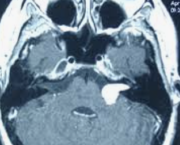

La trompe d’Eustache (du nom du médecin italien, Bartolomeo Eustachi, qui l’a décrite à la Renaissance) est le canal qui fait communiquer la caisse du tympan (derrière le tympan) avec la partie postérieure de la fosse nasale, le rhinopharynx.

Elle s’ouvre passivement à chaque déglutition, permettant d’équilibrer l’air dans la caisse, égalisant la pression atmosphérique de part et d’autre de la membrane tympanique.

Sa taille évolue pendant la croissance, passant de 18 mm chez l’enfant pour atteindre 40 mm chez l’adulte. Parallèlement, de courte et sensiblement horizontale chez l’enfant, elle s’allonge, se porte oblique en bas, en avant et en dedans chez l’adulte, prenant un aspect en accent circonflexe plus ou moins ouvert.

Schéma : Trompe d'Eustache (en jaune)